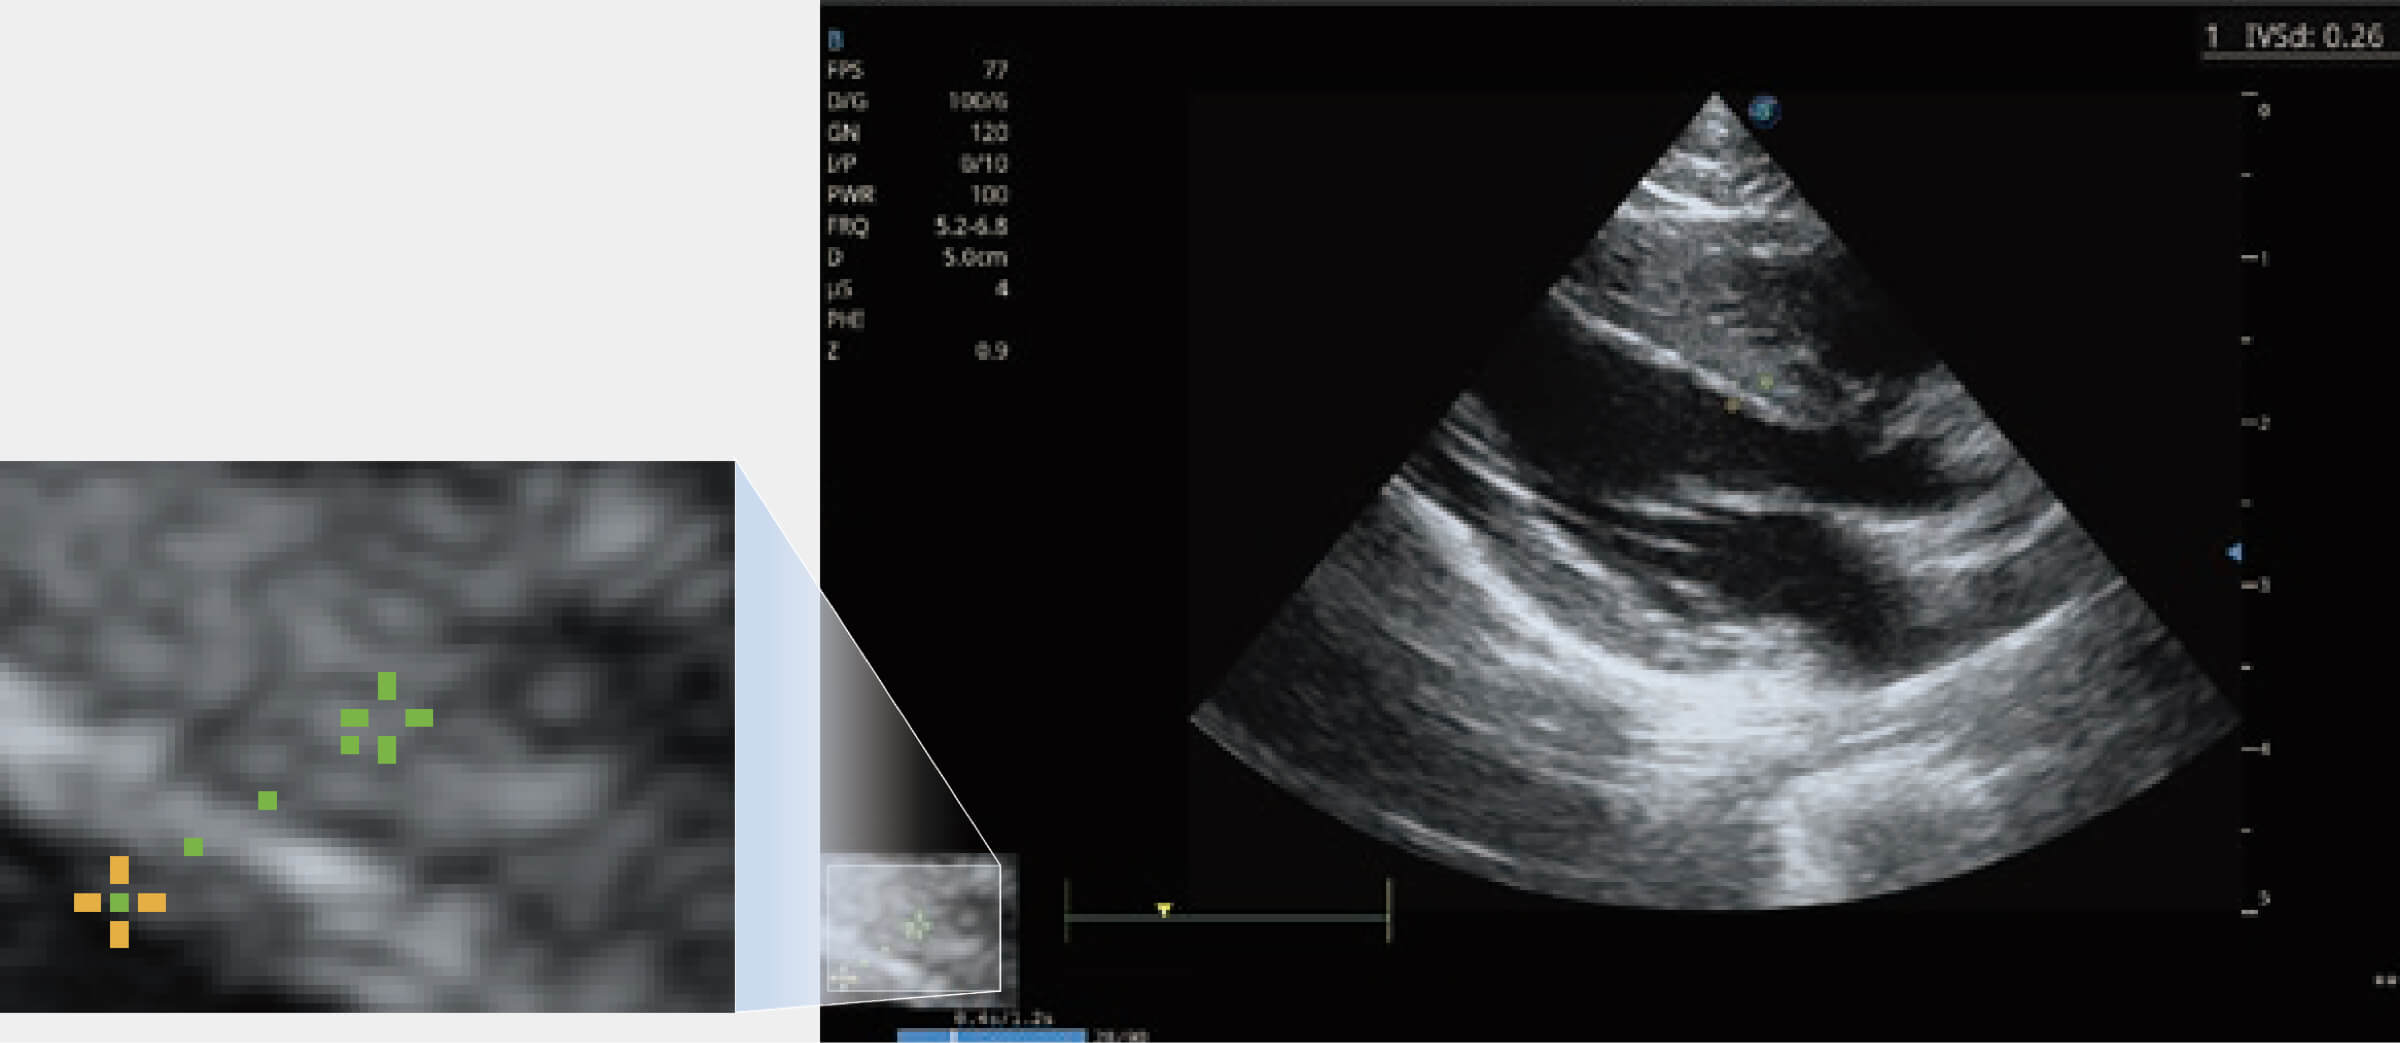

增強(qiáng)穿刺針在動(dòng)物解剖結(jié)構(gòu)中的位置,提高穿刺介入的安全性和準(zhǔn)確性。